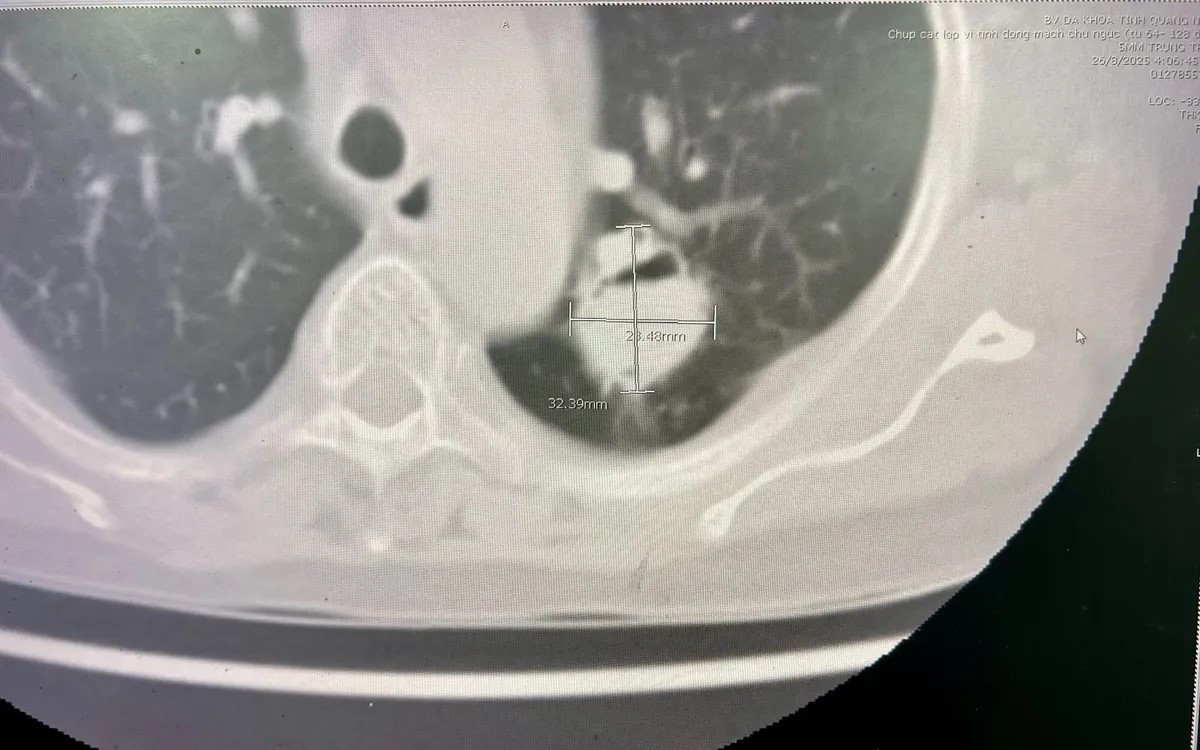

Trong ca mổ, khối u kích thước hơn 3cm nằm sát rốn phổi, dính nhiều vào thùy dưới, thành ngực và động mạch chủ, khiến việc bóc tách trở nên phức tạp. Sau hơn 2 giờ, ekip phẫu thuật đã cắt trọn thùy phổi chứa u nấm, bảo tồn phần phổi còn lại, đảm bảo thông khí tốt.

Hình ảnh chụp X-quang cho thấy khối u nấm phổi kích thước 3,2cmx2,4cm nằm tại thùy trái phổi/Ảnh Bệnh viện Đa khoa tỉnh Quảng Ninh